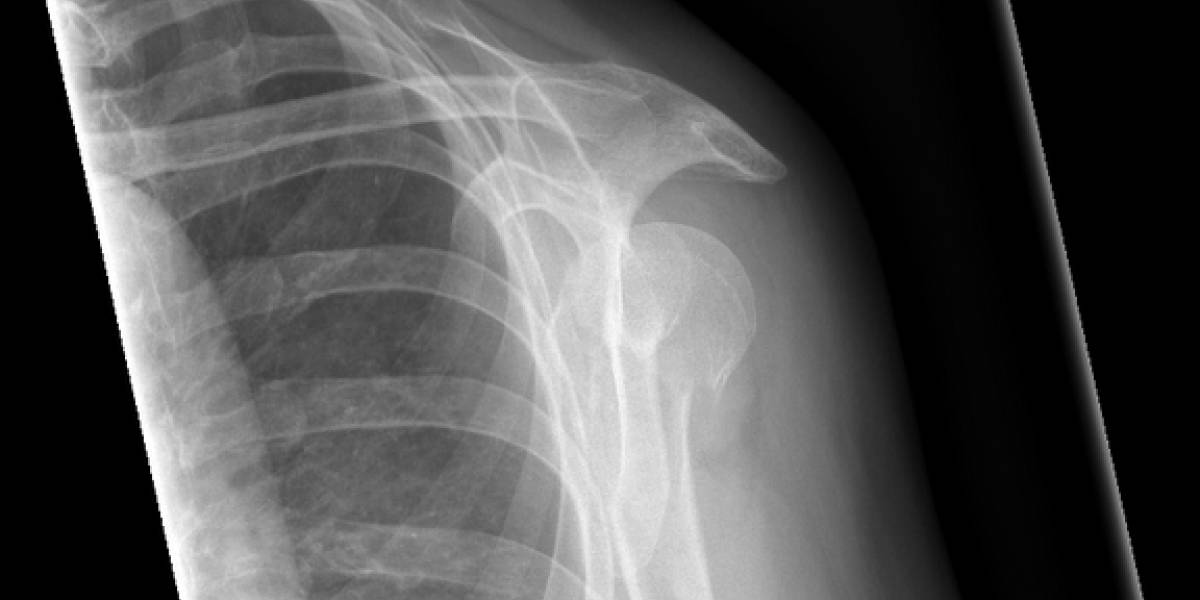

Skulderbrud heler ligeså godt i slynge som ved operation. Røntgenbillede fra Regionshospitalet Viborg.